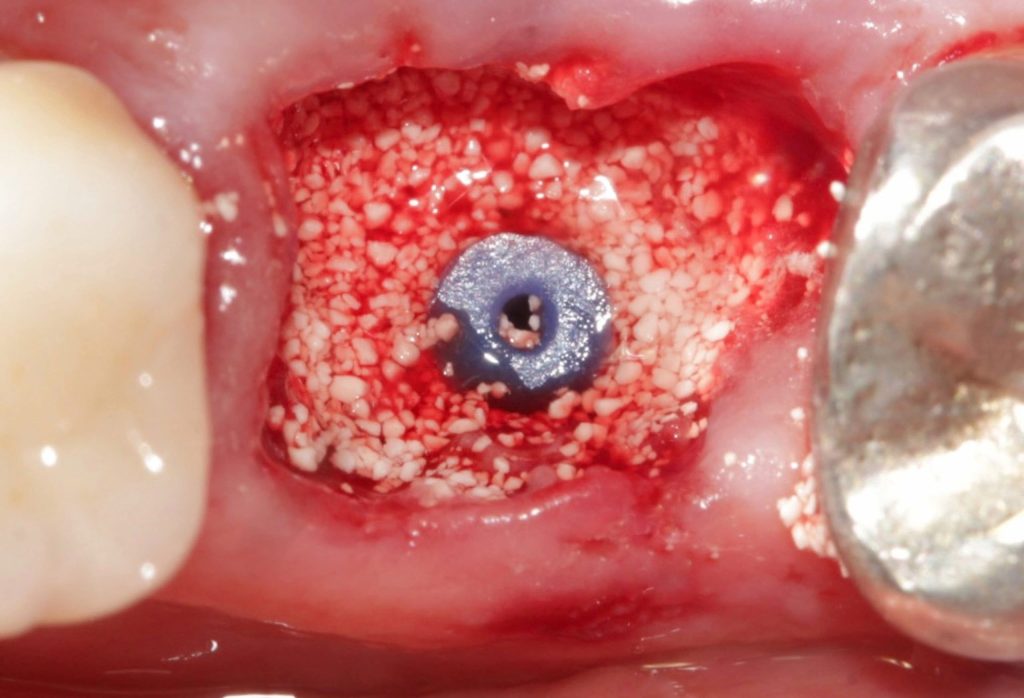

Preenchimento alveolar com enxerto ósseo sintético

Paciente, sexo masculino, 30 anos, compareceu à clínica Naturale Odontologia, cidade de Joinville, apresentando lesão endoperiodontal com envolvimento de furca associada à mobilidade no elemento 46. Optou-se pela regeneração através de biomaterial sintético à base de fosfato de cálcio no mesmo ato cirúrgico da exodontia. A escolha se deveu dada sua excelente praticidade clínica […]

Além da comprovação científica de maior formação óssea em menos tempo, o biomaterial sintético Nanosynt vem sendo aprovado e recomendado por especialistas pelo seu incrível resultado clínico, praticidade e economia. Confira abaixo e experimente você também. Acompanhamento – Dr. Bernardo Passoni “Neoformação óssea em tempo recorde e ainda sem desperdício de material.” Acompanhamento – Dr. Eduardo […]